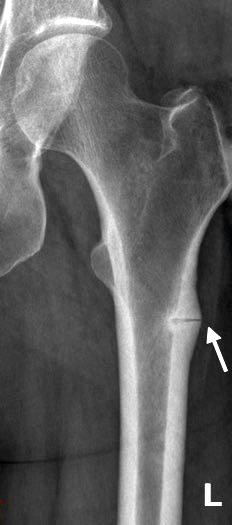

Benämningen atypisk femurfraktur kommer från ett radiologiskt avvikande mönster jämfört med den vanliga osteoporosrelaterade, metafysärt belägna fragilitetsfrakturen. Slätröntgen av den atypiska femurfrakturen visar radiologiska tecken på stressfraktur: en tvärgående frakturspalt, vinkelrätt mot femurs laterala kortex, och en tydlig kallus som ett tecken till att frakturen utvecklats under en tid (Figur 1). En frakturspalt som endast engagerar laterala kortex definieras som en inkomplett fraktur (Figur 2). När frakturen dislokerar, vilket kan ske utan eller efter minimalt trauma, kallas den för komplett (Figur 1). Den mest etablerade definitionen av atypisk femurfraktur föreslogs 2010 [4] av American Society of Bone and Mineral Research och uppdaterades av samma organisation 2014 [5]. Definitionen är i grova drag uppdelad i fem huvudkriterier, varav minst fyra måste uppfyllas för diagnos (Fakta 1). Av de fem huvudkriterierna är ett baserat på anamnestisk uppgift (hur frakturen uppstod, det vill säga utan eller efter minimalt trauma) och resterande på radiologiska fynd.

Figur 1. Komplett atypisk femurfraktur med tvärgående frakturspalt (pil) vinkelrätt i förhållande till benets laterala sida. L= lateralt

Figur 2. Inkomplett atypisk femurfraktur där frakturspalten (pil) är begränsad till kortikalt ben lateralt. L= lateralt